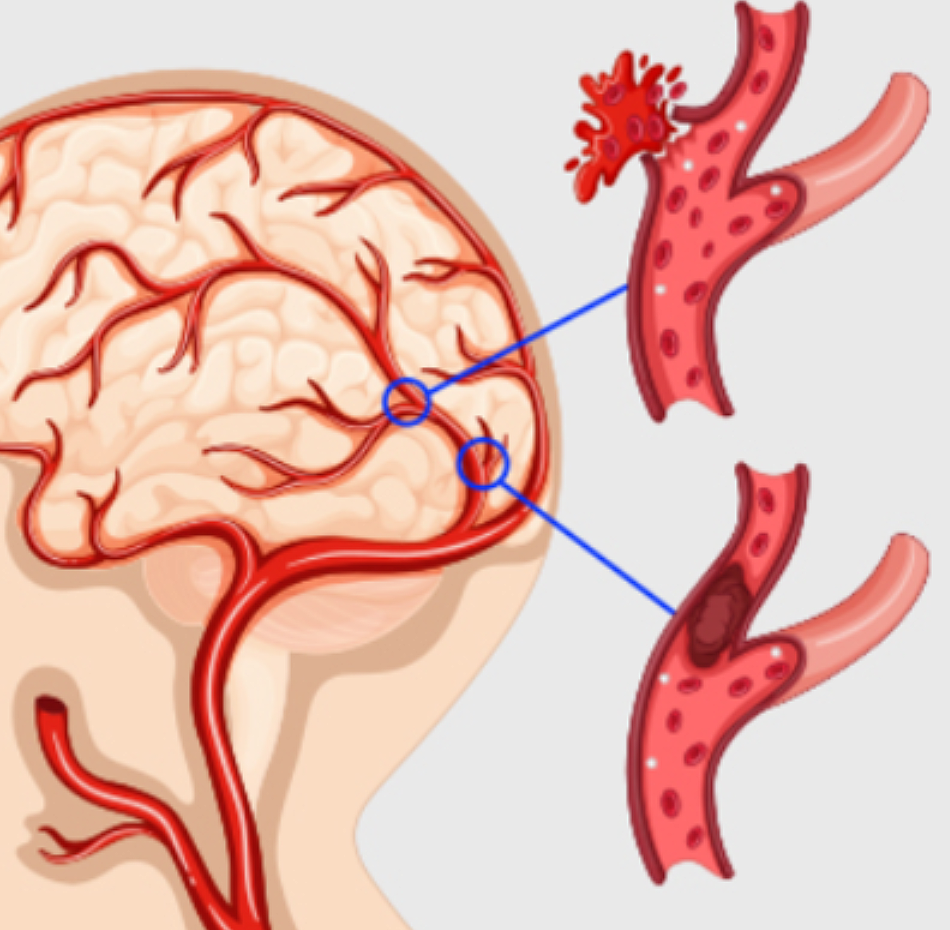

증상이 나타나면 검사를 통해 정확한 진단이 필요합니다. 보통 MRI, 경동맥 초음파 등을 통해 증상을 확인합니다. 뇌의 단층을 촬영하고 뇌혈류 검사와 뇌혈관조영술 등 여러 방법을 통해 질환을 확인합니다.

진단을 받게 되면 증상의 정도에 따라 약물 치료, 혈관 성형술, 스텐트 삽입술, 경동맥 내막 절제술 등을 이용하여 치료합니다. 가장 간단한 방법은 막혀있는 혈관을 뚫어주는 것입니다. 혈전 용해제를 통해 혈류를 개선시켜줍니다. 심장 질환에 의해 나타나거나 혈관 박리 등으로 인해 발생한 경우에는 피의 응고를 막기 위해 항응고제를 사용하기도 합니다.